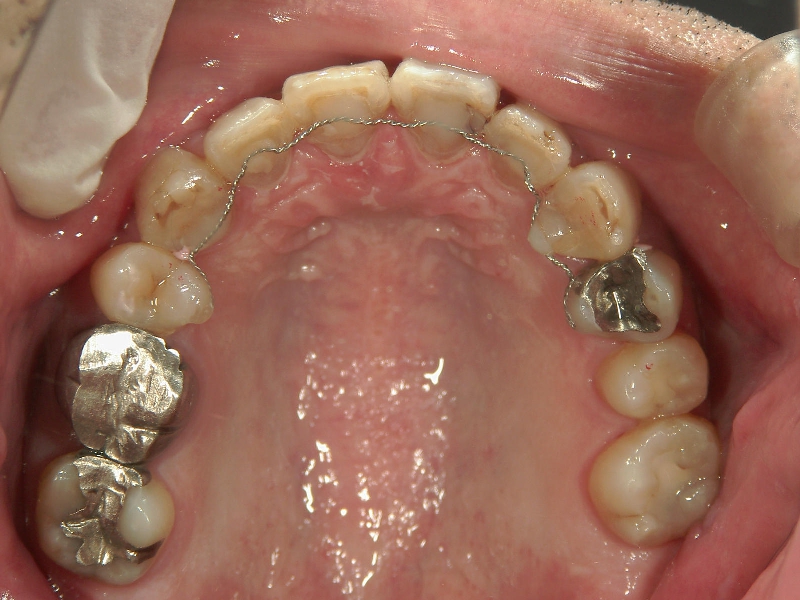

矯正歯科 治療前 右上4番、左右下4番 計3本抜歯し、叢生を改善

矯正_灰色.pngno.22_8175_治療前_上.jpg矯正_灰色.png